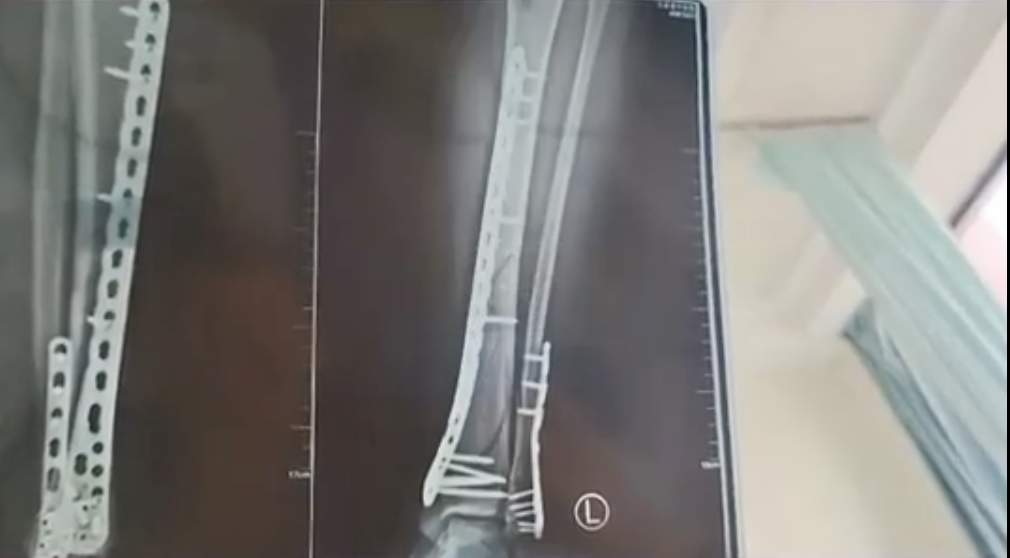

2024年,甘肃兰州的武女士发文称,她穿着鞋底厚达7厘米的增高洞洞鞋下楼,结果不慎崴脚摔倒,造成了左腿粉碎性骨折。武女士介绍,自己的这双洞洞鞋鞋底比较厚,脚掌中间又是凹进去的,她下楼梯时正好踩到了凹进去的地方,没踩稳,整个人的重心往前扑,重量都集中在了腿上。